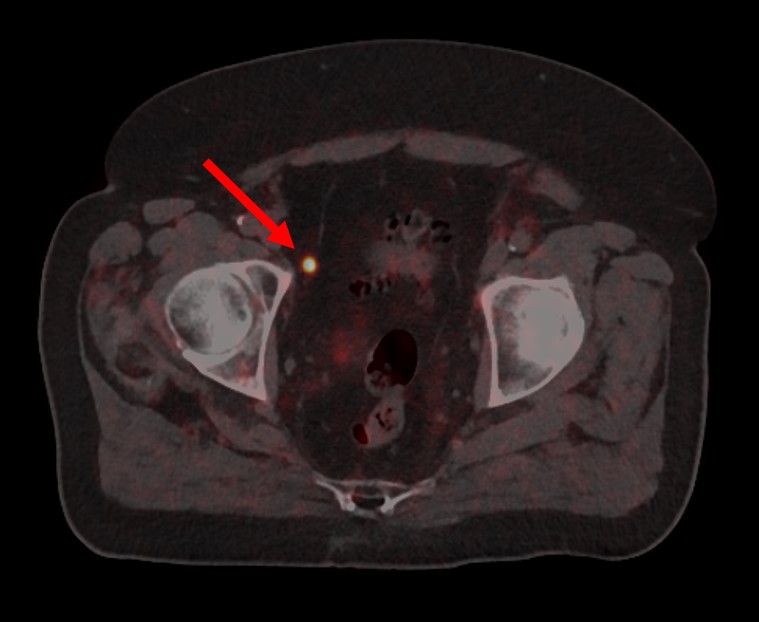

Han ligger i ei seng på det nye PET-senteret i Tromsø. For en time siden ble han injisert med det radioaktive sporstoffet PSMA (prostaspesifikt membranantigen), som nå sprer seg i kroppen. Om noen minutter skal han inn i PET/MR-maskinen. Bildene som tas vil vise om – og eventuelt hvor – det er økt opptak av det radioaktive stoffet i kroppen. Økt opptak kan indikere at kreftsykdommen har blusset opp igjen eller spredt seg.

– Vi kan nå gjøre et mye tryggere valg av behandling. Ved en PET-skanning kan vi stille en mye sikrere diagnose, og vi får bedre informasjon om sykdomsutbredelse. Er det spredning eller ikke? Er det et lokalt tilbakefall? Dette er vesentlige opplysninger som vi får et langt klarere svar på gjennom bruken av PET, sier Bogsrud.

- Isotopene konsentreres i områder der celledeling og emnesomsetning skjer raskest, typisk tumorvev. PET er en funksjonsundersøkelse som påviser grad av sykdomsaktivitet med stor følsomhet.